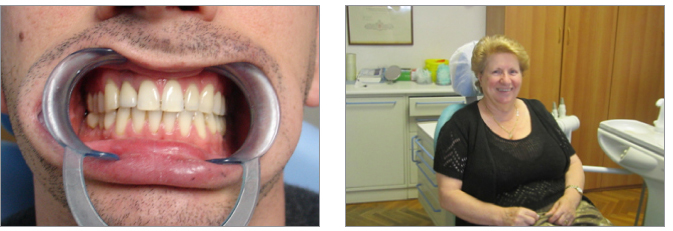

6) Disallineamenti anteriori possono essere risolti con una terapia con mascherine per un maggior confort del paziente adulto

9) L’esecuzione di impianti è indicata nei casi di agenesia dei laterali. E’ necessario tenere conto anche dell’estetica complessiva del volto

11) E’ importante ottenere la collaborazione del piccolo paziente. Prioritaria è la motivazione dei bambini all’igiene dentale